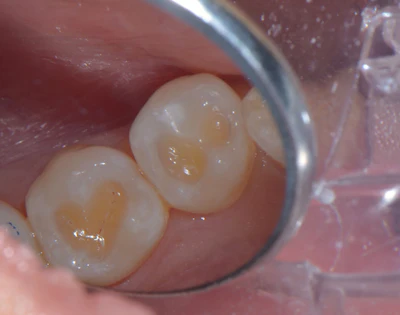

Sixteen Catapult education evaluators participated in the survey, where Visalys Bulk Flow was used in class I, class V preparations, and as a liner and in limited anterior cases. Bulk flowable composites are not generally favored in the aesthetic zone, thus the limited testing in that area. Evaluators noted the balance Visalys Bulk Flow achieved between flowability and stability. Many bulk-flow materials have a very high viscosity, leading to a runny consistency or prone to slumping, but Visalys Bulk Flow held its shape while still adapting well to the preparation. Several evaluators described it as easy to sculpt and particularly useful, especially in small occlusal preparations and cervical lesions (Figures 1, 2).

Figure 1: Preparation of class I caries on two lower premolars.Images and captions courtesy of Dr. Lauren Yasuda Rainey.

Figure 2: Immediate post-op, after placement in class I restorations on both lower premolars.